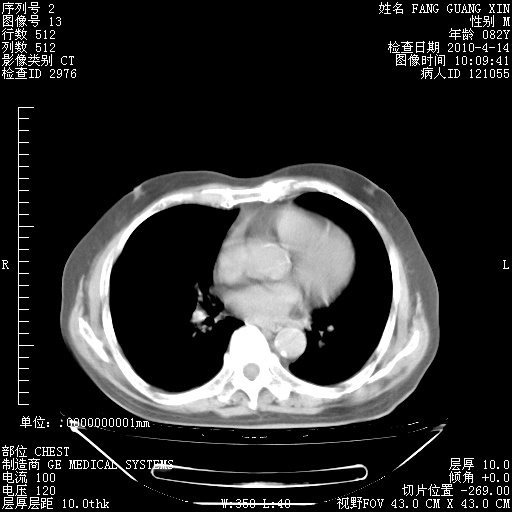

4月14日肺部CT

楼主| 发表于 2010-4-28 16:51 | 显示全部楼层

楼主| 发表于 2010-4-28 16:53 | 显示全部楼层

肺部CT平扫未见异常。